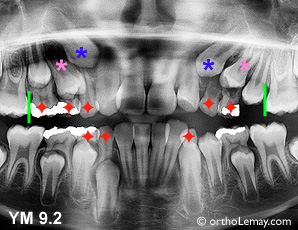

Cas NC

Cas NC : Extractions sélectives des canines supérieures et d’une molaire visant à aider l’éruption des latérales. Les dernières molaires temporaires sont très endommagées (on y voit les grosses obturations métalliques en blanc sur la radiographie) sont mobiles et tomberont sous peu alors la pose d’un mainteneur d’espace serait essentielle pour éviter de perdre davantage d’espace et empirer la situation. Les lignes vertes sont devant les molaires permanentes qui ne doivent pas avancer. (Voir la légende pour identifier les dents)

Cas RV-YM-EB

Cas RV : Mauvaise direction des prémolaires supérieures qui bloquent les canines. L’extraction des canines et premières molaires temporaires accélérera et redirigera l’éruption des prémolaires et aidera indirectement les canines.

Cas YM : Situation similaires mais, vu que la formation des dents permanentes est plus avancée, la deuxième molaire temporaire droite peut aussi être extraite tandis que celle de gauche est déjà tombée par elle-même. Les lignes vertes indiquent qu’il serait indiqué d’utiliser un mainteneur d’espace afin d’éviter la migration des molaires permanentes vers l’avant.

Cas EB : Encombrement et mauvaise direction d’éruption des canines et premières prémolaires supérieures, surtout à gauche. Les extractions aideront les prémolaires supérieures mais aussi les canines inférieures.